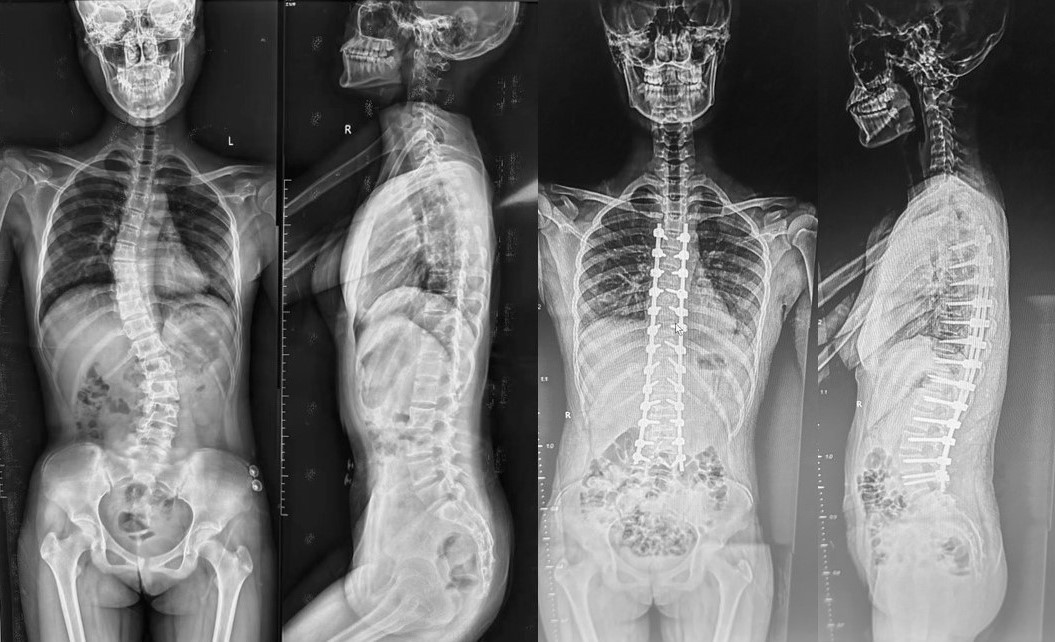

病例1是一名14岁青少年,诊断为腰骶部半椎体畸形,自两年前被确诊后一直佩戴支具治疗,但效果不佳,随着时间推移,体态变形日益明显,脊柱侧凸逐渐加重,感觉双腿一长一短,日常工作和生活受到极大影响。科主任王栋教授组织全科讨论评估患者病情,做了详细的术前评估,并制定了完善的手术方案。由王栋主任、蔡璇副主任及王瑞主治医师为患者实施了经后路腰骶段半椎体切除椎弓根螺钉内固定植骨融合术,手术过程顺利,取得满意的矫形效果,助力患者挺起脊梁(图1)。

病例1:腰骶部半椎体畸形,行半椎体切除短节段固定融合术